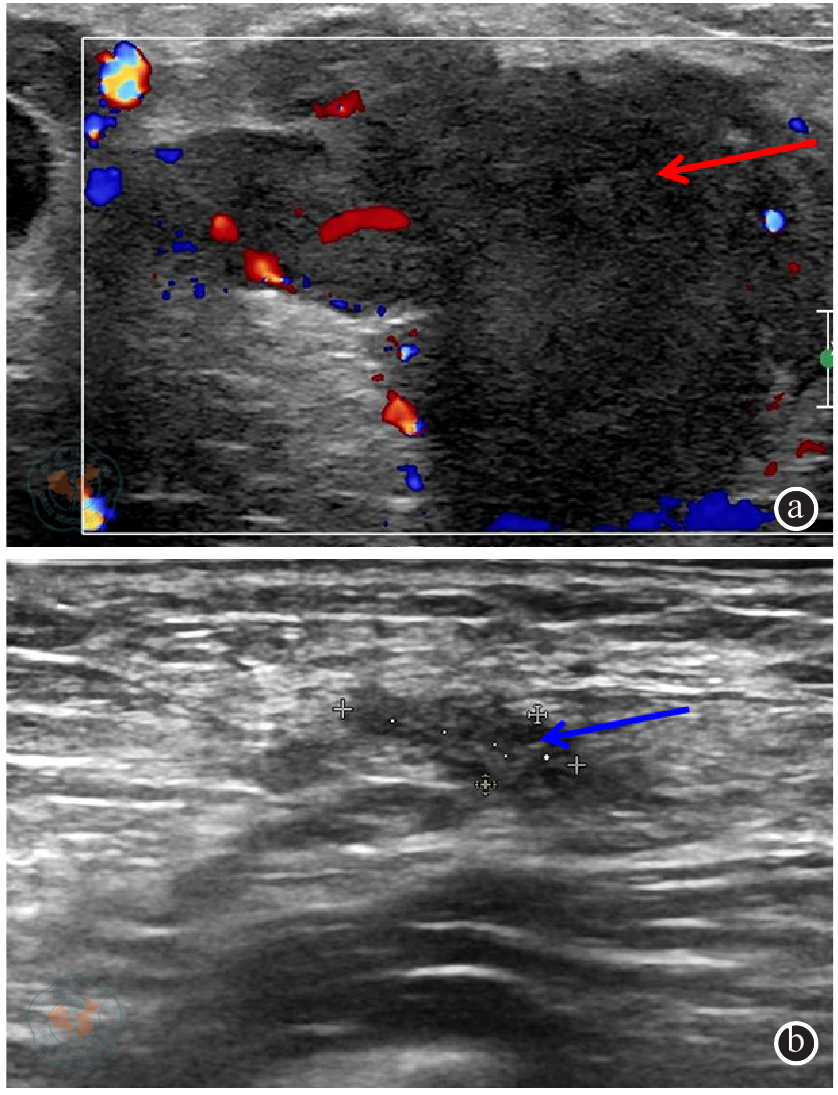

图2 阴茎癌患者影像学检查示双侧腹股沟淋巴结肿大注:红色箭头为右侧腹股沟区融合淋巴结,蓝色箭头为左侧腹股沟区淋巴结